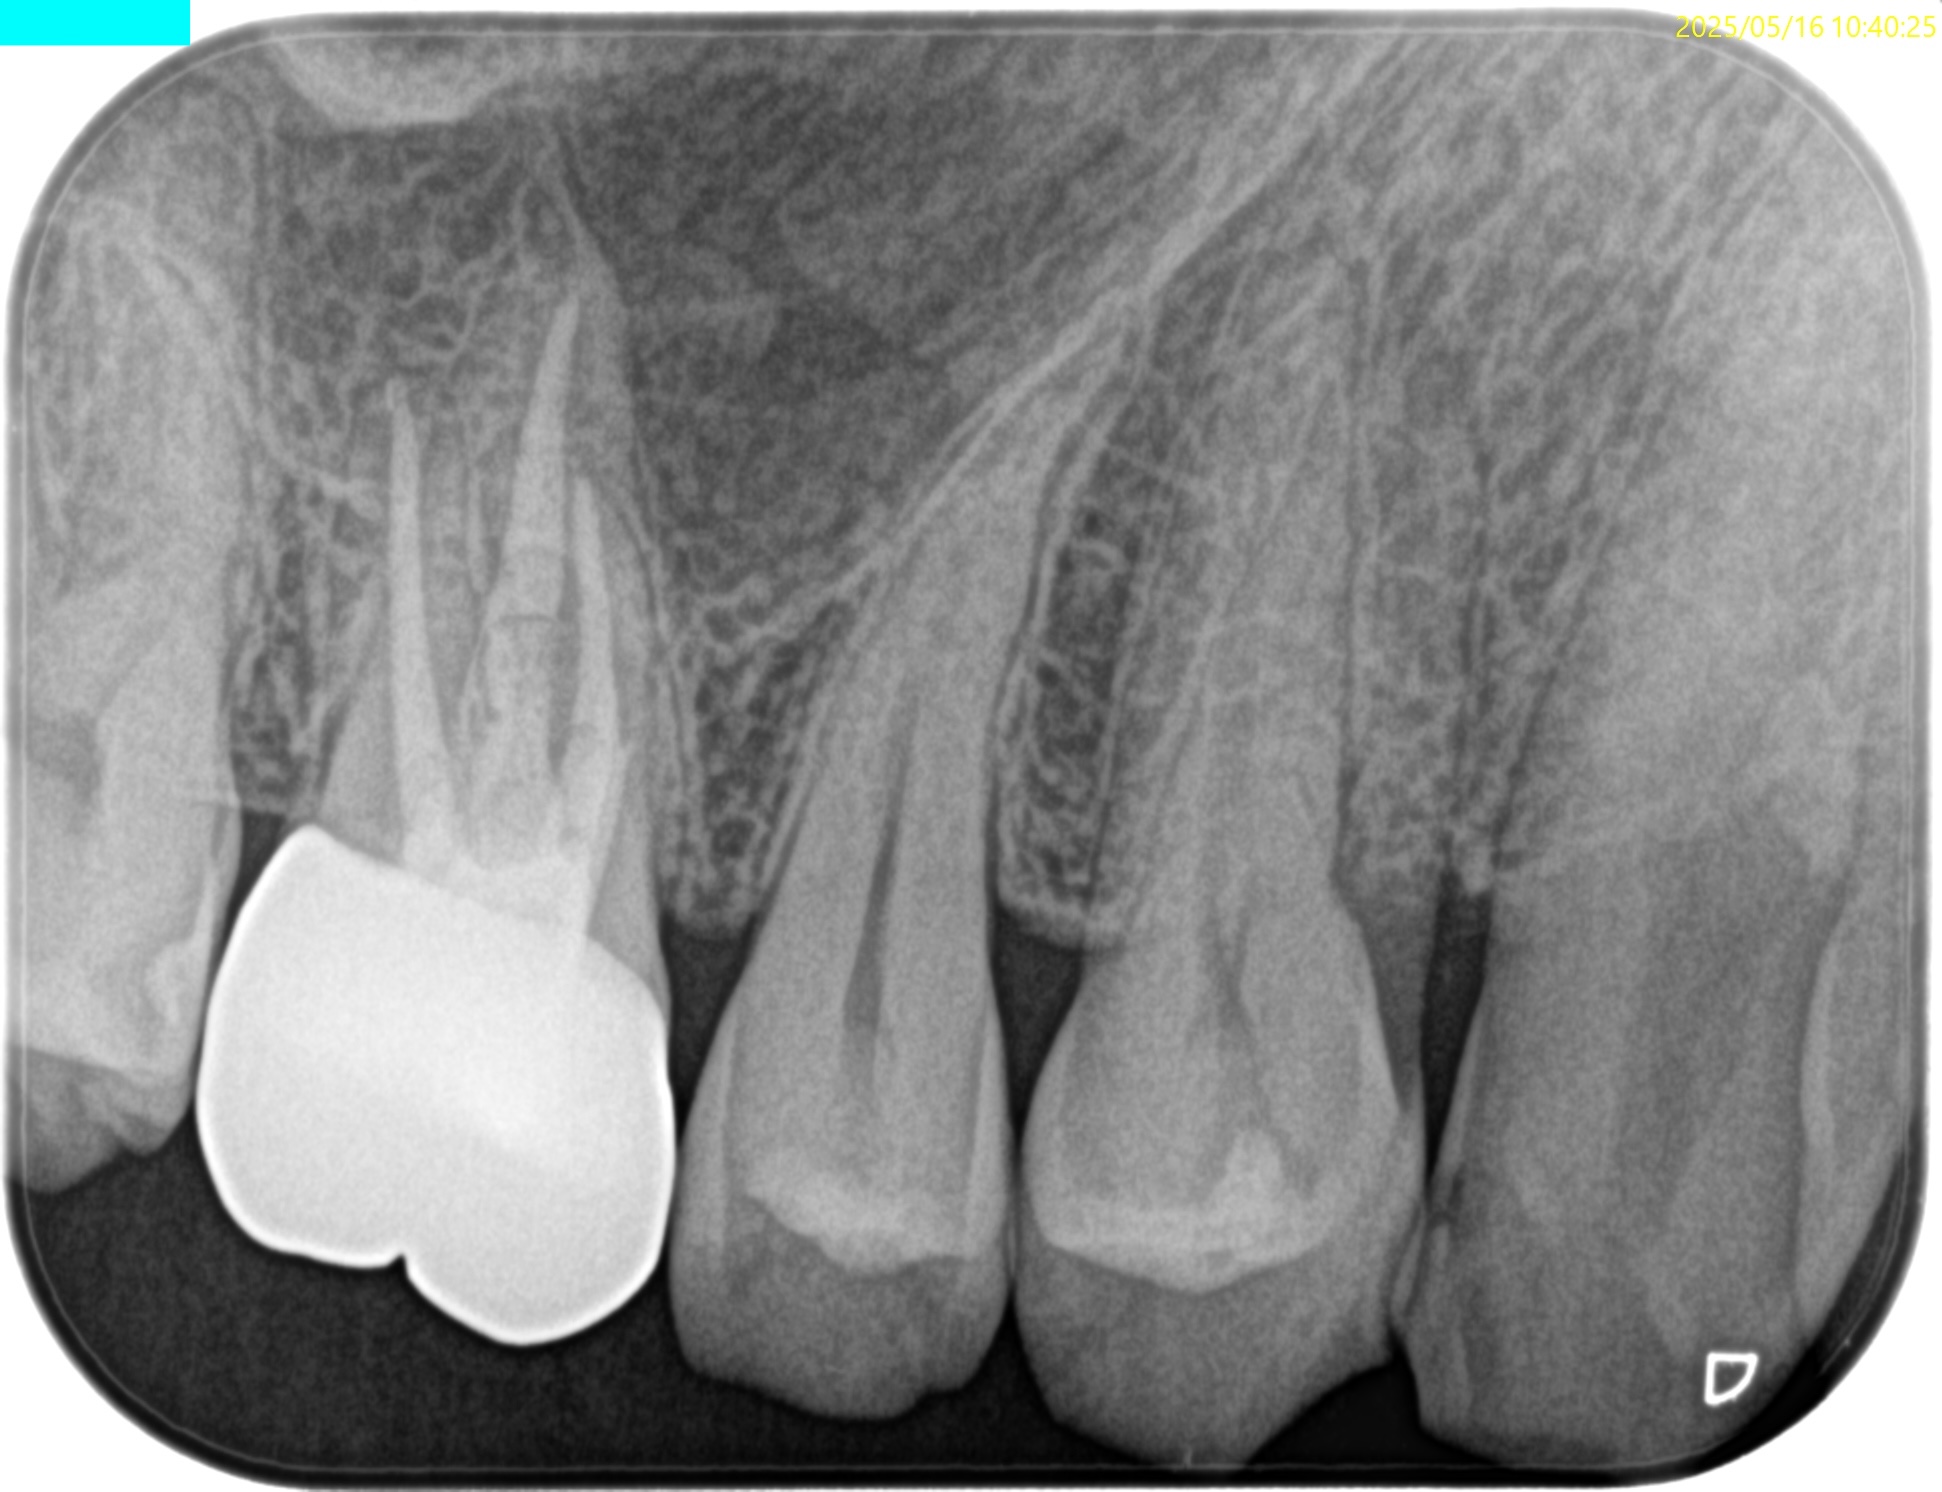

#3 RCT 1.6yr recall(2025.5.16)

術前の臨床症状は喪失した。

初診時と比較した。

初診時の臨床症状は喪失した。